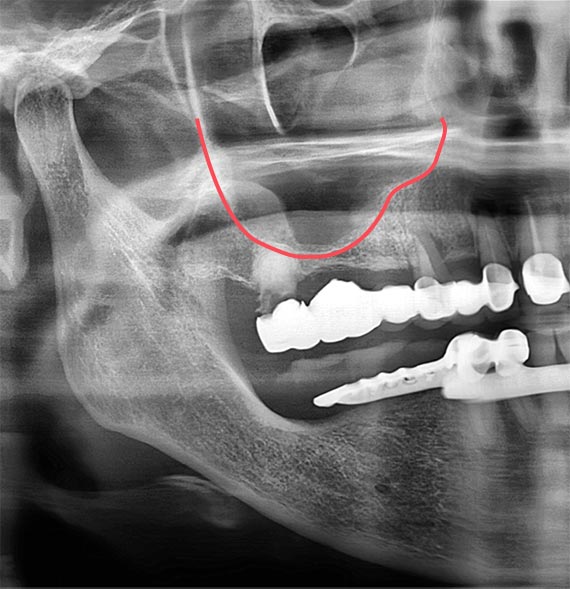

상악의 어금니를 뽑고 오랜 시간이 지난 경우